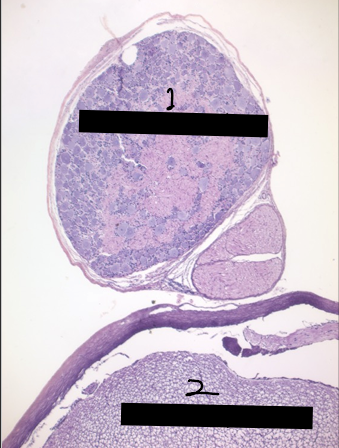

1

dorsal root ganglion

2

section of spinal cord

1 & 2

axons of the dorsal root